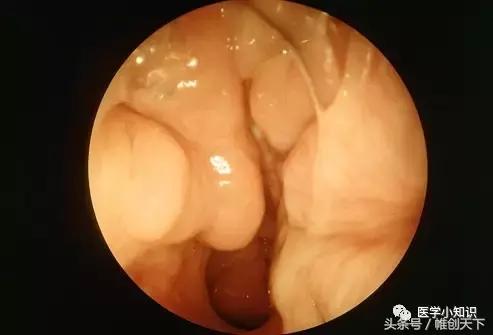

鼻窦长期处于发炎态势使得窦膜加厚、肿胀,鼻腔黏膜出现水肿样改变,形成像葡萄样聚集的鼻息肉(如图所示)。鼻息肉形成后进一步堵塞了鼻窦的引流通道阻碍了粘液的持续流动,进一步加重了鼻窦炎。